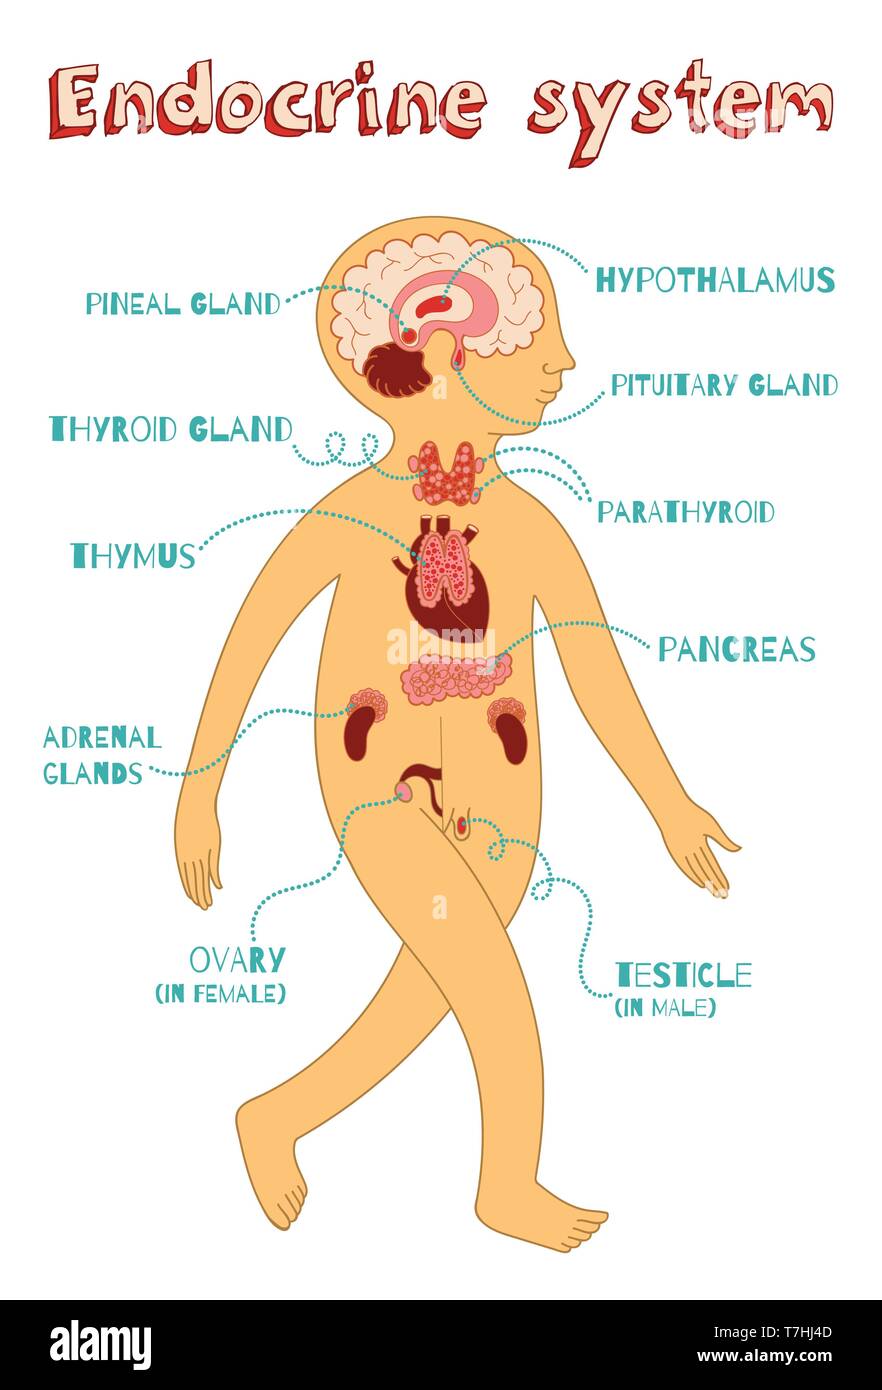

Human endocrine system for kids. Vector color cartoon illustration. Human anatomy scheme. Stock Vectorhttps://www.alamy.com/image-license-details/?v=1https://www.alamy.com/human-endocrine-system-for-kids-vector-color-cartoon-illustration-human-anatomy-scheme-image245635165.html

Human endocrine system for kids. Vector color cartoon illustration. Human anatomy scheme. Stock Vectorhttps://www.alamy.com/image-license-details/?v=1https://www.alamy.com/human-endocrine-system-for-kids-vector-color-cartoon-illustration-human-anatomy-scheme-image245635165.htmlRFT7HJ4D–Human endocrine system for kids. Vector color cartoon illustration. Human anatomy scheme.